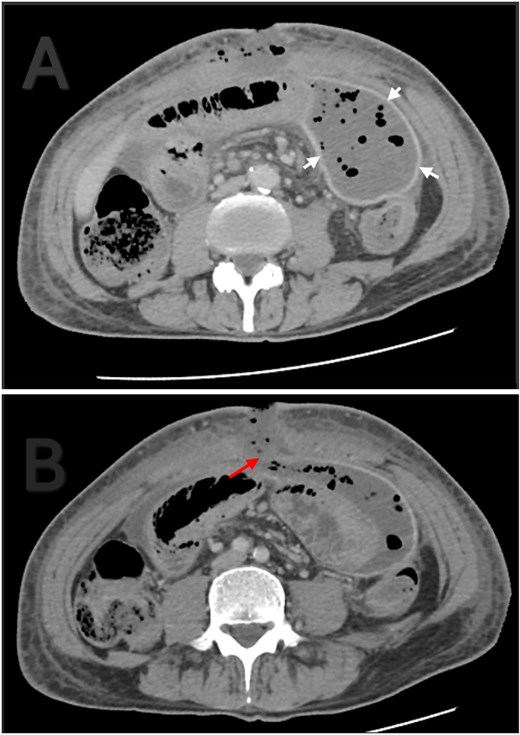

The patient initially had an uneventful recovery and was discharged on postoperative day seven. A week later, he returned with asymptomatic pus discharge from the wound. CT revealed a 15 × 8 × 6 cm encapsulated intra-abdominal collection and small fascial dehiscence without signs of anastomotic leak (Fig. 3). After failed radiological drainage, a vacuum-assisted dressing was applied for 8 days. Follow-up ultrasound confirmed resolution of the collection and closure of the defect. The patient was discharged in stable condition and showed complete wound healing at follow-up.

Contrast enhanced abdominal CT. (A) Thick and well localized capsule surrounding the collection (white arrows). (B) The collection is communicating with the atmosphere through a fascial dehiscence (red arrow).